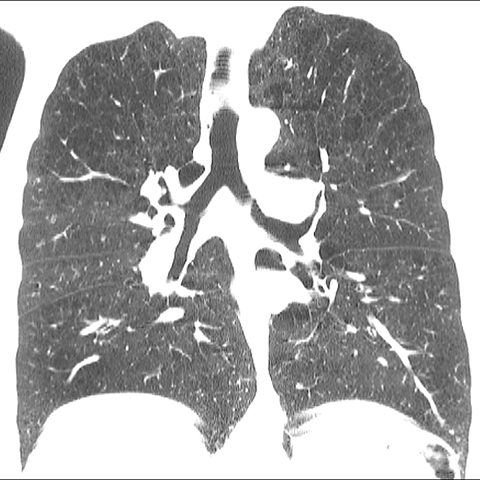

A 62 year-old male presents with chronic shortness of breath (Coronal HRCT). [6 of 6]